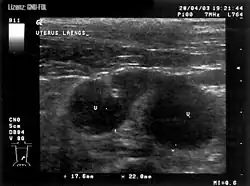

Pyometra

Pyometra (z řec. pyon, hnis, a metra, děloha) je zánět dělohy, při kterém dojde k naplnění děložní dutiny hnisavým výpotkem. U většiny savců včetně člověka vzniká pyometra rozvojem zánětu děložní sliznice, neboli endometritidy. Výjimkou je fena a kočka, kde hnisavý zánět dělohy vzniká na podkladě hormonálně podmíněných změn v děloze nekastrovaných a nenakrytých fen a koček po proběhlé říji.

U ženy se může pyometra rozvinout při endometritidě, zánětu děložní sliznice. Endometrium zduřelé v důsledku zánětu může uzavřít kanál děložního hrdla a tak se v děložní dutině může hromadit hnis.